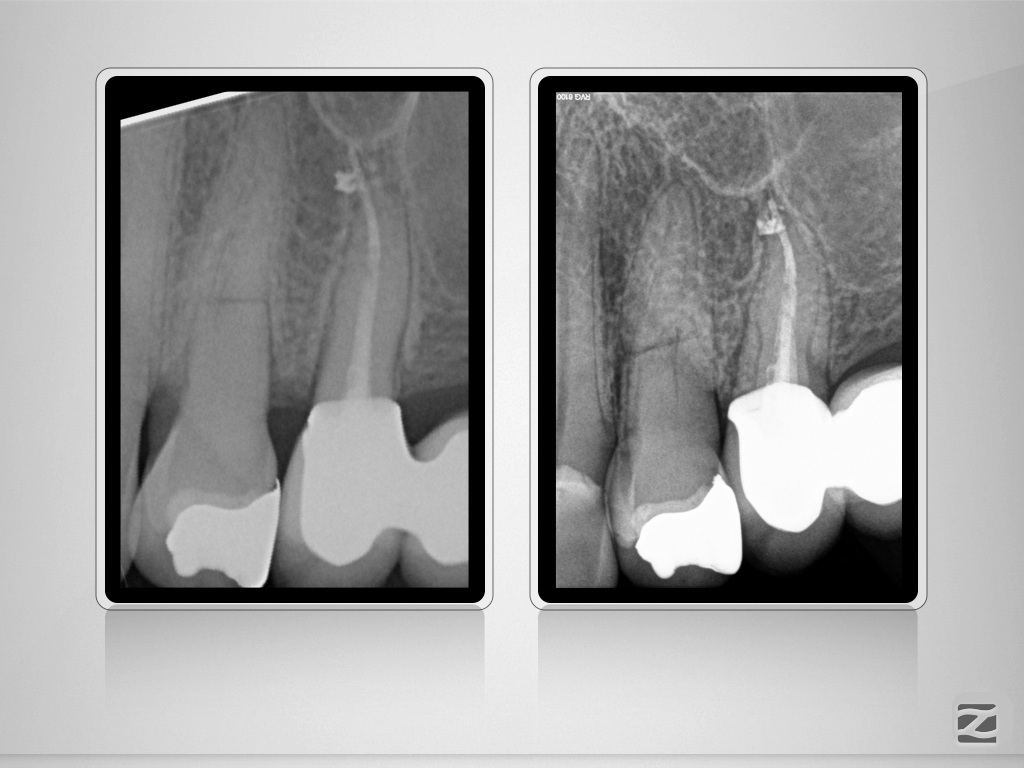

24D.002

Und nun? Die Auflösung.